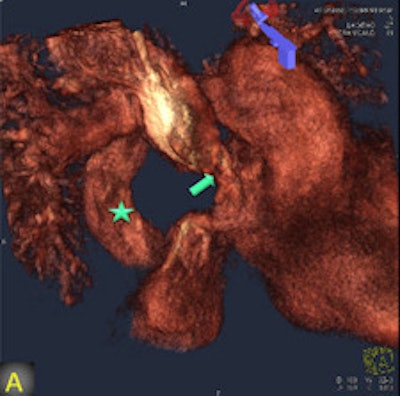

FD-CT, combined with image fusion to overlay 3D reconstructions on fluoroscopic images during catheter-based interventions, was useful -- and occasionally irreplaceable -- for deciphering the complex anatomy of congenital heart disease, wrote authors Dr. Martin Glöckler, Dr. Andreas Koch, and colleagues from University Hospital Erlangen in Erlangen, Germany.

"The fusion of 3D reconstructions with live fluoroscopic images during catheterization may help to find the ideal fluoroscopic angulation during catheter-based interventions, to achieve difficult vascular crossings by the wire or the catheter, to choose the most appropriate material for catheterization, and to define and control optimized positioning of implants such as stents or valve prostheses," Glöckler and colleagues explained.

"One unique feature of FD-CT is the possibility of merging 3D reconstructions with the real-time fluoroscopic image," a potentially useful way to identify ideal C-arm angulations for achieving wire passage for atypical vascular crossings, and to optimally depict the implant position of coils, plugs, stents, and valves," Glöckler and colleagues wrote. "In fact, image fusion of 3D reconstructed FD-CT images with the live fluoroscopic image was frequently rated as 'very useful' (57.4%)."